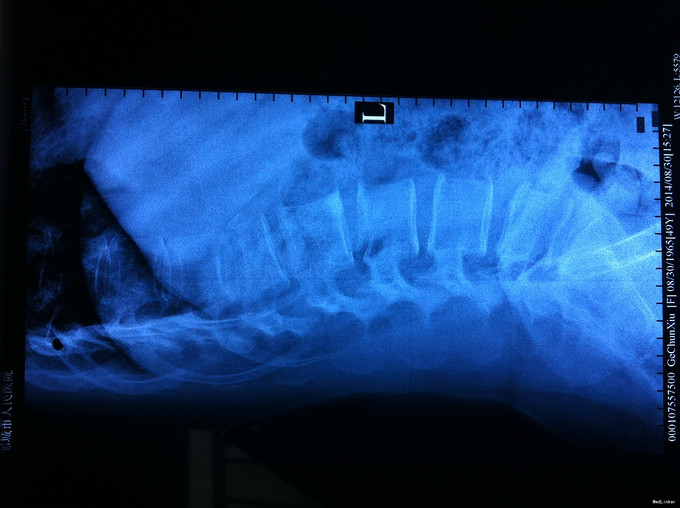

专科查体无下肢神经损伤表现:腰部叩痛,腰部活动受限,双下肢感觉无异常,双下肢肌力4-5级,双侧膝腱反射++,跟腱反射+,双侧巴氏征阴性, X-ray:腰1椎体骨折,累及前中柱,腰3椎体骨折。CT:腰1、3椎体骨折,累及中柱。MR:腰1、3骨折,新鲜骨折。影像学检查提示腰1椎体骨折较重。